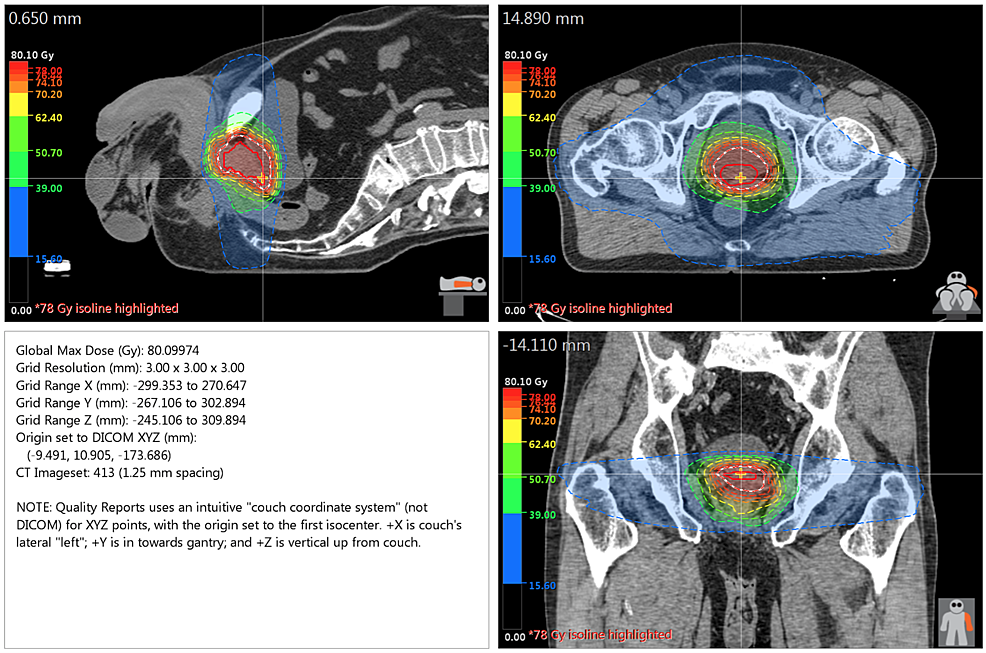

Radiation Therapy

The patient was treated in the supine position with RT delivered to both the prostate and seminal vesicles via volumetric modulated arc radiotherapy (VMAT) (78 Gy/2 Gy fractions at a 100 percent isodose line with two full arcs and 10 MV photons) with an Elekta Infinity linear accelerator (LINAC) (Elekta AB; Stockholm, Sweden). A Pinnacle treatment planning system (Phillips Radiation Oncology Systems; Fitchburg, WI) was utilized. Figure 3 outlines the dose distribution of the RT plan.

A dose volume histogram (DVH) that compares rectal irradiation for a VMAT plan with a rectal spacer as against without a rectal spacer can be seen in Figure 4. A diagnostic CT scan was utilized to simulate the VMAT plan without a rectal spacer for the same patient.

Notably, the maximum dose (Dmax) received by the rectum was 60.4 Gy with spacer placement as compared to 78.7 Gy without the hydrogel spacer, with dosimetric benefits most evident at higher doses. A more detailed comparison of toxicity to the rectum can be found in Table 1. Of note, given that the VMAT plan without the spacer was simulated using a diagnostic CT, no bowel prep was utilized and this may be responsible for the differing isodose lines and, subsequently, the relatively higher doses received by larger rectal volumes with the rectal spacer.